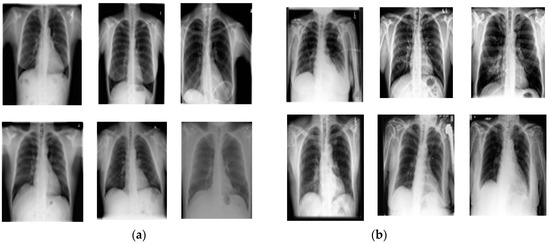

4.1.1. The Chest X-ray Dataset